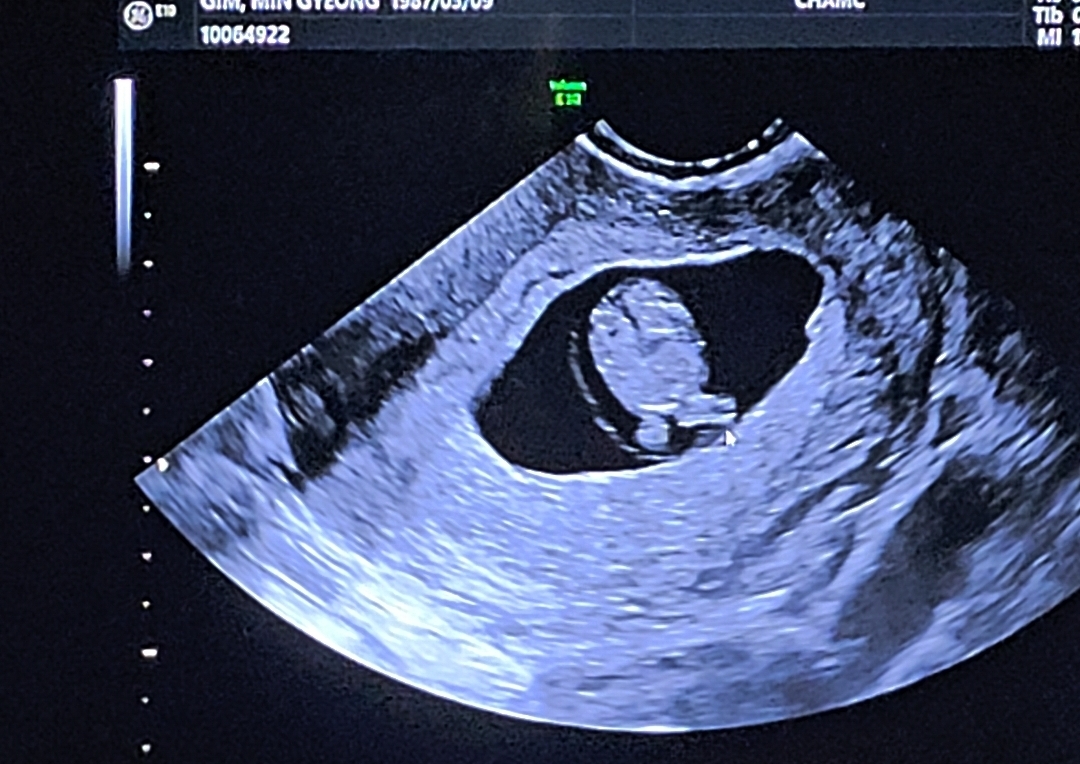

마미님들 9주차 초음파보다가 딸인것같아서

9주차면 생식기 생겼지 않나요? 다리사이에 암것도 없어서 딸인것같은데 어때보여요?

12주이상은되야.성볗알수잇어요!!